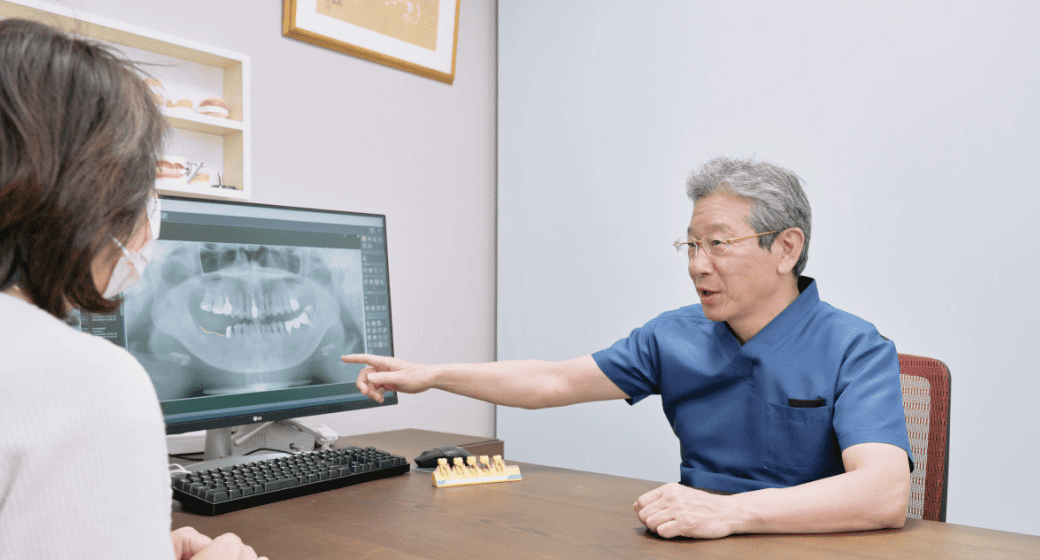

当院では、CT撮影による3D画像診断をもとに、骨の厚みや高さ、密度を立体的に把握。必要があれば、骨造成を取り入れたインプラント治療計画をご提案しています。

大杉歯科医院では、CTや口腔内検査によって十分な診査を行い、適応可能と判断できた方にのみご提案しています。

患者さまの「もう一度しっかり噛めるようになりたい」「笑顔に自信を持ちたい」といった想いに寄り添い、最適な治療方法を対話と診断を通して一緒に導き出す――それが、当院の変わらぬ姿勢です。